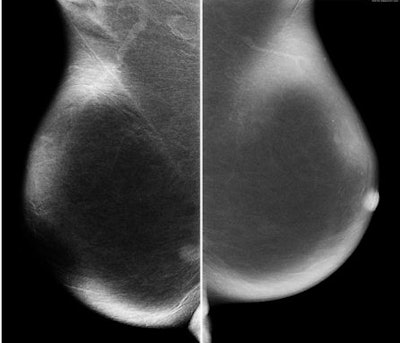

![]() |

| Enhancement after contrast. |